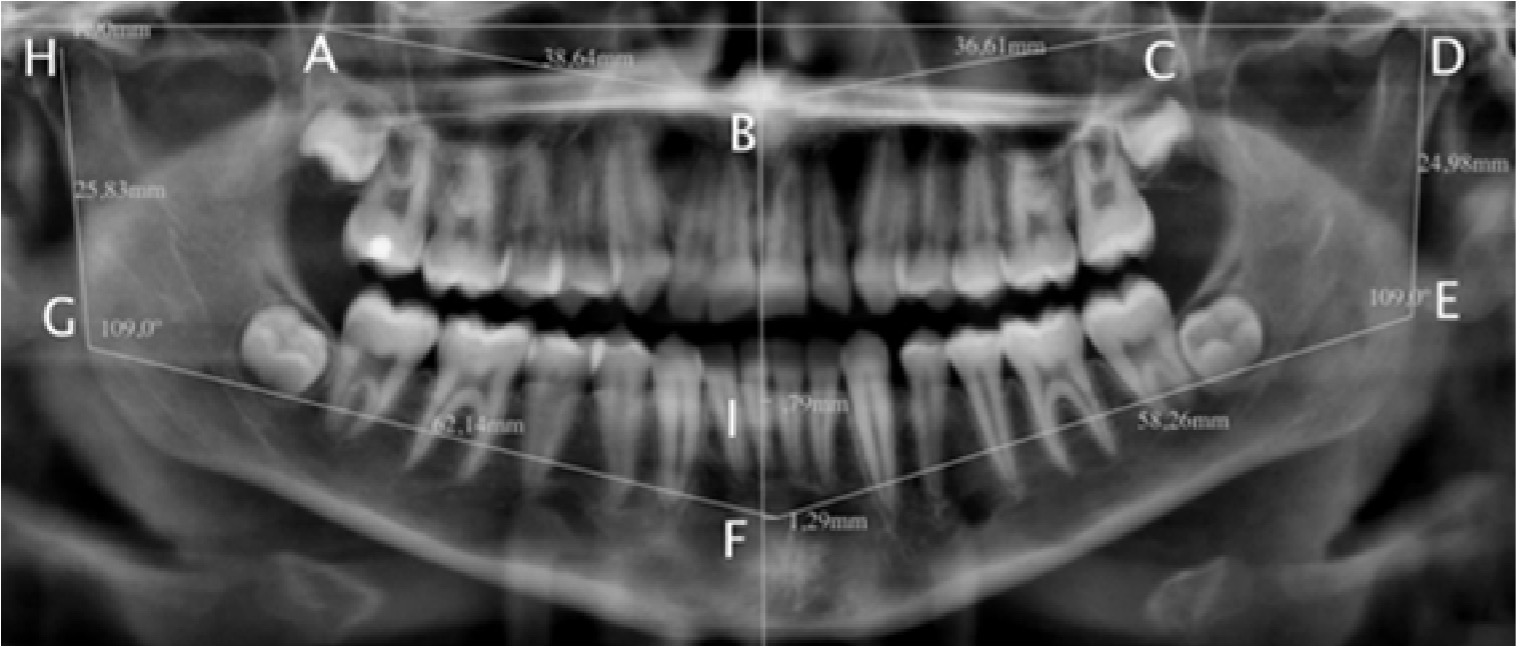

Se seleccionaron radiografías panorámicas para evaluar comparativamente el crecimiento craneofacial, empleando mediciones lineares angulares predeterminadas a puntos anatómicos topográficos maxilomandibulares como se muestra en la figura 1.7

Figura 1: Evaluación cefalométrica maxilomandibular. A. Relación maxilomandibular, B. Aspecto posterior del maxilar derecho, C. Espina nasal anterior, D. Aspecto posterior del maxilar izquierdo, E. Cabeza de la mandíbula izquierda, F. Ángulo mandibular izquierdo, G. Fosa mental, H. Ángulo mandibular derecho, I. Cabeza de la mandíbula derecha, vértice de la cresta alveolar inferior.

Los niños con SPW presentaron aumento de la extensión de la rama mandibular con una diferencia estadísticamente significativa en comparación con los controles (p = 0,03). Aunque se observaron diferencias no significativas en la otra evaluación cefalométrica, los niños con SPW mostraron una reducción en el crecimiento craneofacial horizontal. La Figura 2 muestra el crecimiento craneofacial en promedios comparativos.

Figura 2: Leyendas: evaluación del crecimiento craneofacial. Los niños con SPW mostraron un aumento vertical estadísticamente significativo en la rama mandibular. Se observaron diferencias no significativas en la reducción general del crecimiento craneofacial.